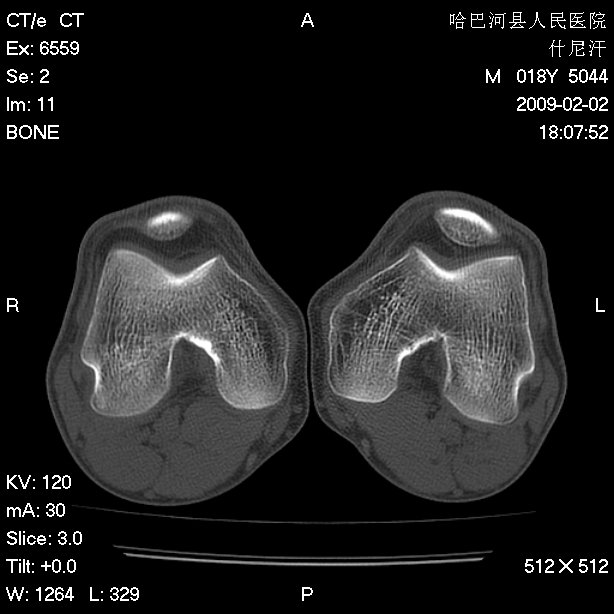

标题: CT17889:外伤后右膝关节反复疼痛3年余 [打印本页]

标题: CT17889:外伤后右膝关节反复疼痛3年余

ct未见明显异常。关节腔未见明显积液,半月板未见明显撕裂。但最好还是mri看看韧带及半月板情况。